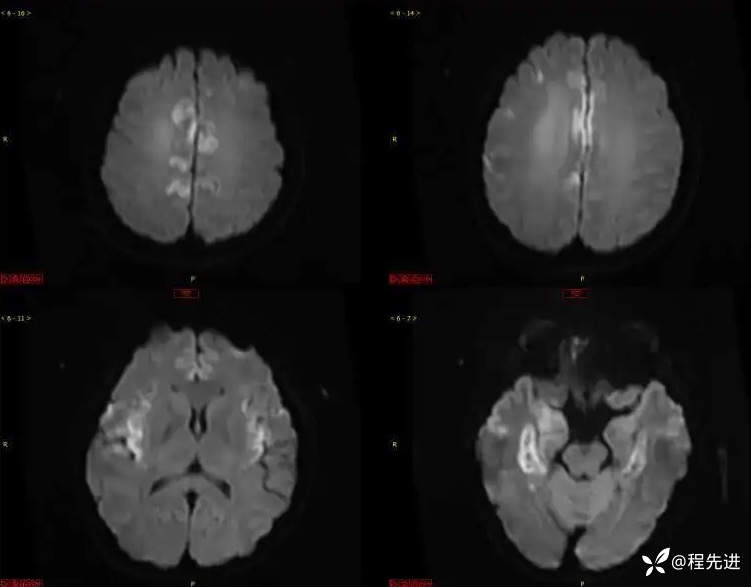

DWI、ADC: